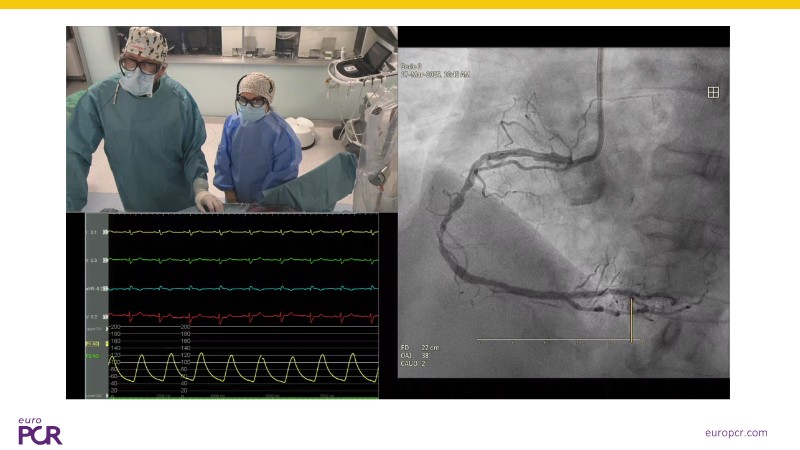

Watch this EuroPCR 2025 session to learn how intravascular lithotripsy (IVL) is transforming the management of coronary artery calcification (CAC). Discover the new CALC roadmap, a comprehensive framework guiding device selection and treatment strategies based on calcium burden, anatomy, and patient gender. Follow a real-world clinical case demonstrating how to optimize treatment pathways using IVL as a first-line approach, supported by exciting new clinical data from multiple studies. Gain practical insights on sizing IVL balloons with intracoronary imaging to maximize procedural success and safety, and explore how this technology can improve outcomes by simplifying calcium modification during PCI.

- To learn with a real-world clinical case how to optimise treatment pathways for CAC, supported by new clinical data